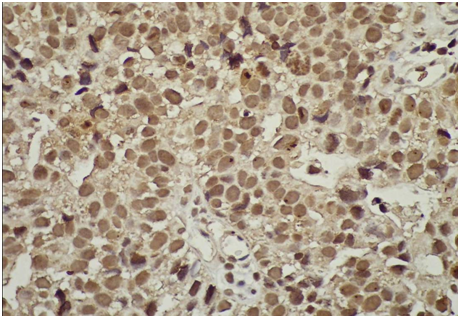

Survivin protein was overexpressed in urinary bladder cancer tissues. Positive or negative survivin overexpressed was determined by IHC staining. Cells that had positive survivin overexpression, revealed with brown nuclei, where cells that had negative survivin overexpression, revealed with blue nuclei. The intensity of the staining was designated as

1. Negative (0) if less than 10 % of the malignant cells were stained (Figure 3).

2. Weak (+) if 10-50 % of the malignant cells were stained (Figure 4).

3. Moderate (+ +) if 50-80 % of the malignant cells were stained (Figure 5).

4. Strong (+ + +) if over 80% of the malignant cells were stained (Figure 6).

Figure 5 Intermediate grade survivin positive immunostaining many nuclei stained in brown color (blue arrow) due to the over expression of survivin protein inside these nuclei, the other nuclei stained blue (black arrows) as counterstaining (X400).